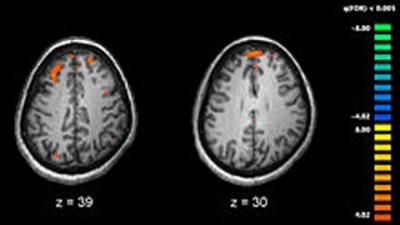

New York, Mar 4 (IBNS): Reach for the hand of a loved one in pain and not only will your breathing and heart rate synchronize with theirs, your brain wave patterns will couple up too, according to a new study.